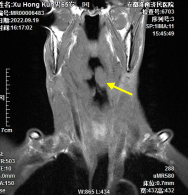

患者脑血管病变引发的慢性微量出血。

图解:磁敏感加权图像中黄色箭头指示的黑色圆点为脑内出血灶。